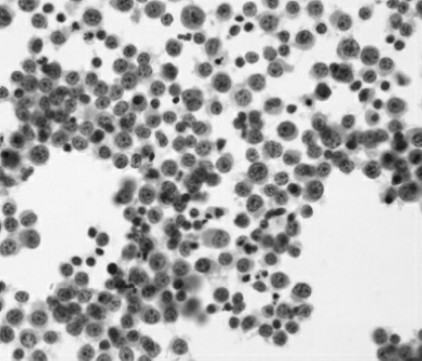

Fig.12-2 Microscopic examination of aplastic anemia

Anemia is defined as a significant reduction in the mass of circulating red blood cells.As a result,the oxygen binding capacity of the blood is diminished. Because blood volume is normally maintained at a nearly constant level,anemic patients have a decrease in the concentration of red cells or hemoglobin in peripheral blood(Fig.12-1,12-2).Hemoglobin and hematocrit levels vary with the age of the individual and,in adults,with gender.The values in women of childbearing age are 10%lower than those in men.Anemic patients'values are more than one standard deviation below the mean values for their gender. However,because of the wide range in normal hemoglobin and hematocrit levels,it is often difficult to document mild anemia.